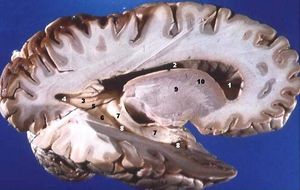

축삭돌기는 신경계의 주요 전달선으로, 다발을 이루어 말초 신경계에서는 신경을 형성하고, 중추 신경계에서는 신경로를 형성한다. 피질 뉴런에서 나온 수초가 있는 축삭돌기는 뇌의 백질을 구성하며, 신경 세포체가 포함된 대뇌 피질의 회백질과 대조적으로 흰색 외관을 띈다. 소뇌에서도 유사한 배열을 보인다. 수초가 있는 축삭돌기 다발은 중추 신경계의 신경로를 구성하며, 뇌의 정중선을 가로질러 반대쪽 영역을 연결하는 곳을 교련 섬유라고 한다. 이 중 가장 큰 것은 두 개의 대뇌 반구를 연결하는 뇌량이며, 약 2천만 개의 축삭돌기를 가지고 있다.[4]

신경계에는 수초가 있는 축삭돌기와 수초가 없는 축삭돌기 두 가지 유형이 있다.[5] 수초는 지방 절연 물질 층으로, 신경교 세포의 일종인 슈반 세포와 희소돌기아교세포에 의해 형성된다. 말초 신경계에서 슈반 세포는 축삭돌기의 수초를 형성하며, 중추 신경계에서는 희소돌기아교세포가 절연 수초를 형성한다.[5] 수초화는 도약 전도라고 하는 특별히 빠른 전기적 임펄스 전파를 가능하게 한다.피질 뉴런에서 나온 수초가 있는 축삭돌기는 뇌의 백질을 구성하는 신경 조직의 대부분을 형성한다. 수초는 신경 세포체가 포함된 대뇌 피질의 회백질과 대조적으로 조직에 흰색 외관을 부여한다. 소뇌에서도 유사한 배열을 보인다. 수초가 있는 축삭돌기 다발은 중추 신경계의 신경로를 구성하며, 반대쪽 영역을 연결하기 위해 뇌의 정중선을 가로지르는 곳을 교련 섬유라고 한다. 이 중 가장 큰 것은 두 개의 대뇌 반구를 연결하는 뇌량이며, 약 2천만 개의 축삭돌기를 가지고 있다.[4]

피질 뉴런에서 나온 수초가 있는 축삭돌기는 뇌의 백질을 구성한다. 수초는 신경 세포체가 포함된 대뇌 피질의 회백질과 대조적으로 조직에 흰색 외관을 부여한다. 수초가 있는 축삭돌기 다발은 중추 신경계의 신경로를 구성하며, 반대쪽 영역을 연결하기 위해 뇌의 정중선을 가로지르는 곳을 교련 섬유라고 한다. 이 중 가장 큰 것은 두 개의 대뇌 반구를 연결하는 뇌량이며, 약 2천만 개의 축삭돌기를 가지고 있다.[4]